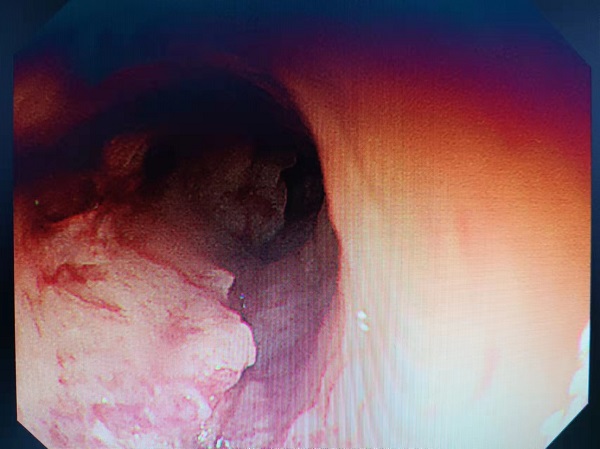

该患者因为肿瘤梗阻食管,管腔变狭窄,反复呕吐无法进食,被诊断为食管癌晚期,已失去手术时机。患者家属为解决日常进食,特来医院消化内科求诊。经过医生团队认真讨论,结合患者实际情况,在征得家属同意后,对其实行了胃镜下覆硅胶膜食道支架植入术。

图:食管管腔(手术前)

通过支架植入,患者可以依靠支架的弹性作用,扩张狭窄部位,膜阻止肿瘤向管腔内生长,术中选择超过病灶长度的支架,使支架在病灶两端均突出1-2cm,防止肿瘤生长超过支架,再次堵塞管腔,从而延长支架的作用时间。当天手术顺利,患者可以进食,达到了手术预期效果。